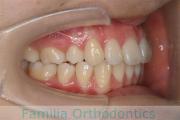

No.22V-029

- 叢生

- 上顎前突

- 19歳

- 男性

- 8448

- FEA 022

- 92万円

でこぼこを治したいということで来院されました。上下左右から親知らずも第一小臼歯も抜歯が必要で、歯科矯正アンカースクリューを併用して大臼歯を後ろに引っ張りながらの治療でした。3年弱、35回程度の通院が必要でした。

叢生が著しく、後戻りのリスクがあります。またアンカースクリューが必須のため、もしもスクリューが安定しないと、治療が難しく長くなってしまう恐れがありましたが、幸い脱落は見られませんでした。